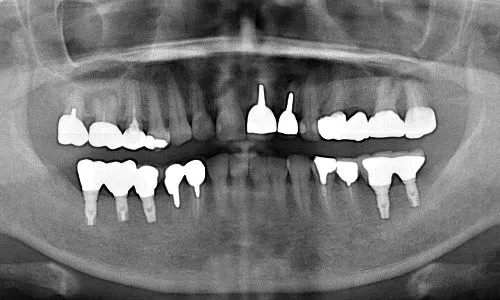

症例②

| 主訴 | 食事ができない |

| 診断名 | 咀嚼障害 |

| 年齢 | 58歳 |

治療に用いた装置(治療法) | 上顎:オールオン6 |

| 部位 | 上顎:右上7・右上5・右上2・左上4・左上5・左上6 下顎:右下7・右下6・左下5・左下6・左下7 |

| 治療期間 | 1年 |

| 治療費用 | 上顎:3,800,000円 下顎:2,310,000円 |

| リスク・副作用(治療に関する) | 腫脹しびれ |